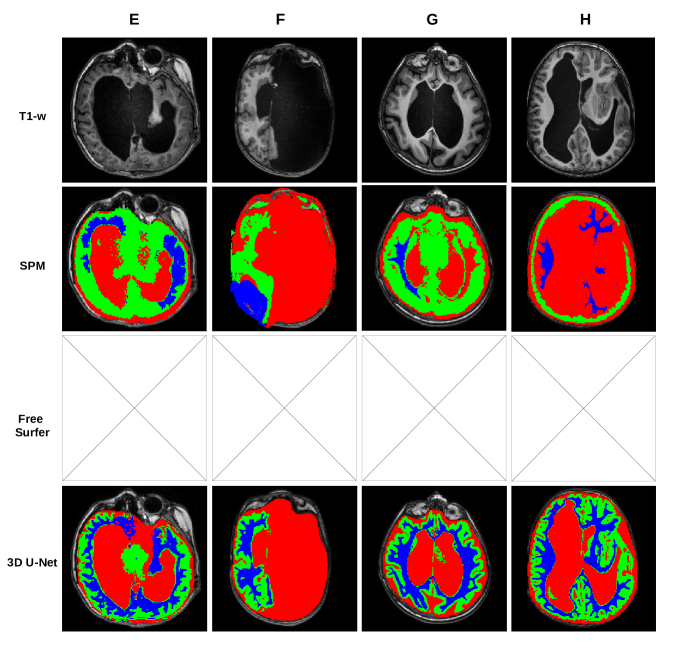

In Figure 1, we show a paradigmatic set of axial slices segmented by FSL, ANTs and the 3D U-Net, from patients with ACC, i.e. from 4 of the 12 subjects described in Section 2.2. Similarly, in Figure 2, we report paradigmatic axial slices segmented by those methods, from 4 of the subjects with complex cerebral distortions. For the segmentations of all methods, we re-labeled as CSF all the voxels inside the brain mask of each patient that were incorrectly segmented as background. In both figures in the last row, for each subject, we highlight a detail of the slice for one of the segmentation methods (indicated with a dashed square, above in the same column). Such details are discussed in Section 5.

Figure 2: First row: T1-weighted MR images of 4 subjects (E, F, G and H) with complex cerebral distortions. Below, the related tissue segmentations (GM in green, WM in blue and CSF in red) of the following pipelines: FSL (2nd row), ANTs (3rd row) and 3D U-Net (4th row). In the 5th row, for each subject, we show the enlarged view of one of the segmentations, indicated above with a dashed yellow square. White arrows point to the highlights discussed in Section 5.

Figure 2 shows that, in case of complex malformations and severe parenchymal distortion, FSL and ANTs are unreliable and incur in major macroscopic errors, as opposed to 3D U-Net which performs vastly better. In cases of severe ventricular dilatation and distortion (E and H), FSL fails to segment the cortex, which is wrongly labelled as CSF. In case F, the CSF collection that replaces the left hemisphere is misclassified as the cortex. In G, FSL fails to properly segment the pachygyric (i.e. with a reduced number of gyri) cortex. Finally, some intensity inhomogeneities in the deep ventricular CSF are misclassified as GM (E and G). With ANTs, which is based on priors, the pipeline is forced to segment WM, GM and CSF in the missing hemisphere (F) or when the anatomy is highly irregular. In all of these cases, the pipeline misplaces structures (E, G, H) or segment structures that are actually missing (F). The 3D U-Net outperforms FSL and ANTs in all cases (e.g. G), with few mistakes. The main issues are: i) the mislabeling of signal inhomogeneities in the deep CSF (E, same as FSL), and the segmentation of a subtle layer of GM at the border between lateral ventricles and WM (H, as done in ACC cases). Care must be used in evaluating CSF/WM interface in cases of brain malformations because, at this level, heterotopic GM nodule may occur.